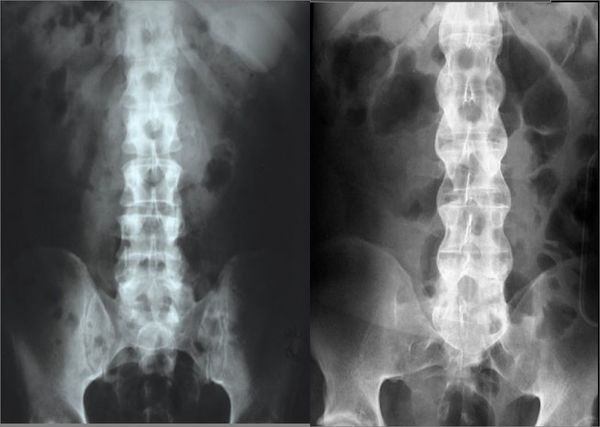

此病常常侵犯年轻男性。“医生误诊是由于此病初发时还未出现关节 ...